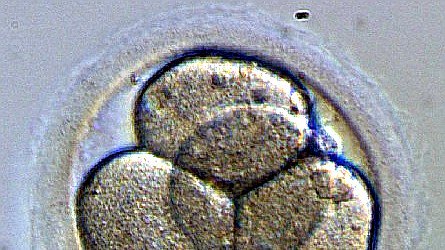

لا يعدُّ ريبريكوف معروفاً بأعماله في تعديل الجينات. فعند البحث عن منشوراته، ستظهر في الغالب تقارير حول المؤشرات الحيوية لأمراض اللثة. ولكنه قام في أكتوبر الماضي بكتابة تقرير تم فيه تطبيق أداة كريسبر لتعديل الجينات على الأجنة البشرية الناتجة عن التلقيح الاصطناعي، وهي واحدة من نحو عشر تجارب في هذا المجال على الإطلاق.